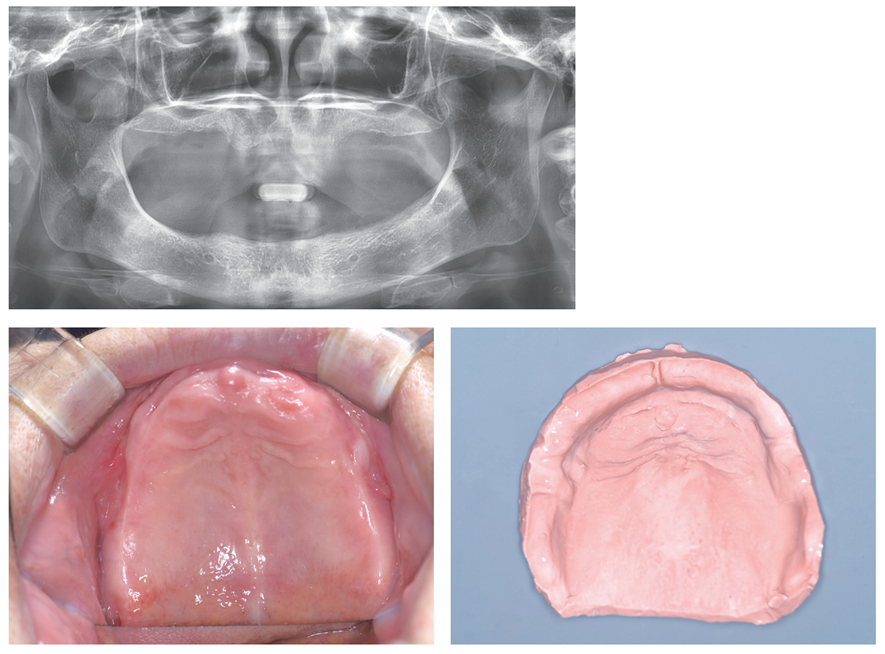

파노라마상에서 상악 치조제 볼륨이 매우 적다.

하악은 치조정이 매우 낮고 협측으로 너무 평탄하다. 하악 협측 부위에서 부착치은이 많이 부족하다.

VD와 CR이 정확한 treatment denture를 계획하였다.

Treatment denture에서 정확한 VD와 CR을 얻으려면 gothic arch tracing이 필요하다.

Gnathometer M을 사용하기로 하였다.